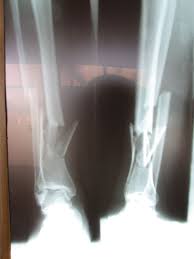

pada pemeriksaan di radiologi tidak semua pasien yang datang untuk foto rontgen dalam ke adaan yang umum atau 'normal' 'terkadang kita dihadapkan dengan situasi dengan pasien yang tidak biasa atau 'tidak normal' tetapi disinilah salah satu tantangan dalam menghadapinya , mungkin ini beberapa contoh kasus yang tidak biasanya..